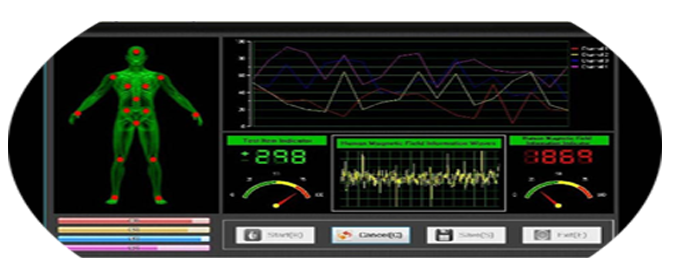

Preventive health care must be planned and executed ahead of time, even when illness is absent."Our scanning techniques provide in-depth know how of the functioning of all the vital human organs and helps in predicting and identify the illness beforehand or during its existence there by giving right direction to the treatment of the patient for the restoration of health to perfection." Unique combinations of treatment to revitaiize the autonomics nervous system nof the body by stimulating flow of vital energy in spine and eliminating all toxins of the body. Quantum Magnetic Resonance Body Analyzer Multilingual Sub Health USA (With CE Standard) The Quantum Health Analyzer Have 41 Reports